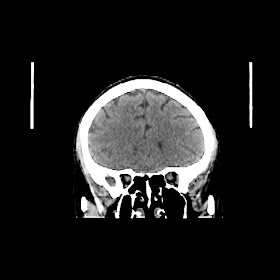

A 50 years old woman with headache, back pain, ghabrahat